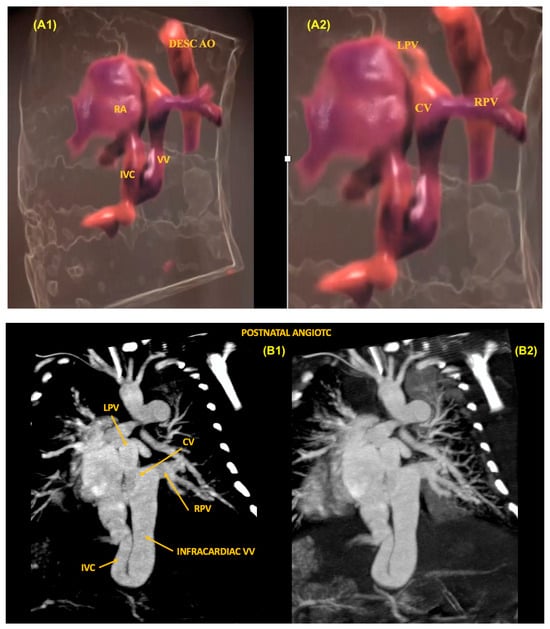

The identification of anomalous pulmonary vein connections can be difficult in the fetus, especially in the partial forms. Considering that the total forms of anomalous drainage of the pulmonary veins are a critical CHD, prenatal diagnosis is crucial to improve the prognosis of these patients. In this setting, it is essential to identify the presence of one or more pulmonary veins draining into the left atrium during routine cardiac ultrasound. To rule out this diagnosis, it is possible to identify the presence of left and right pulmonary veins draining into the left atrium in the 4C view with the aid of color Doppler. In total anomalous pulmonary venous return (TAPVR), all the pulmonary veins drain directly into the morphologically right atrium or through a systemic vein. In these cases, the imaging techniques are very important diagnostic tools for the identification and anatomical detailing of the anomalous venous return. Based on the level of the anomalous connection, TAPVR is generally classified into four major types: supracardiac (Type I), cardiac (Type II), infracardiac (Type III) (Figure 25), and mixed levels of connections (Type IV) [57].

Figure 25.

Total Anomalous Pulmonary Vein Return (TAPVR) Type III (infracardiac). (A1,A2) HDlive Flow technique showing a descending collecting vein with venous confluence (collecting chamber) in a fetus with an infracardiac form of TAPVR. (B1,B2) Postnatal computed tomography angiography of this case, confirming the findings of prenatal cardiac ultrasound. RA: right atrium; LPV: left pulmonary vein; RPV: right pulmonary vein; CV: collecting venous; Desc Ao: descending aorta.; VV: vertical vein; IVC: inferior vena cava.